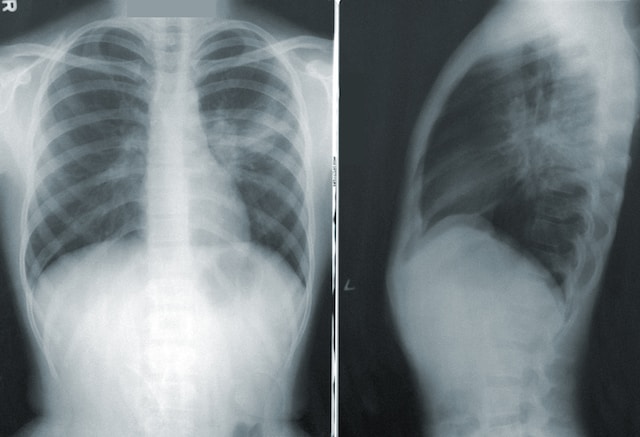

More Adults Should be Screened for Lung Cancer, American Cancer Society Says

Nearly five million additional people are recommended to get screened for lung cancer under an updated guideline from the American Cancer Society, which expanded its recommendations to include older adults who smoke or formerly smoked — no matter how long ago they quit smoking.

Previously, the American Cancer Society recommended annual lung cancer screening for adults ages 55 to 74 with at least a 30 pack-year smoking history who either currently smoke or quit smoking less than 15 years ago. Now, the organization says how long ago you quit smoking should no longer be a factor in whether you get screened for lung cancer. Read more from KSL here.